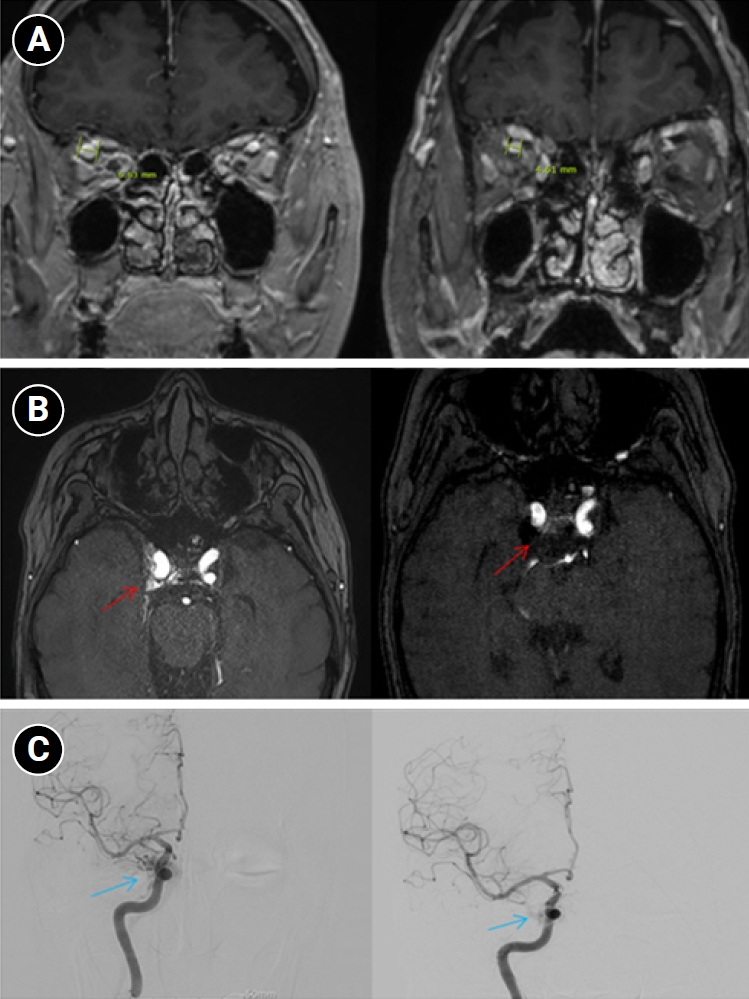

Baseline hematology and chemistry—including complete blood count, electrolytes, renal/hepatic indices—and coagulation tests (prothrombin time/international normalized ratio, activated partial thromboplastin time) were within reference limits. Erythrocyte sedimentation rate and C-reactive protein were normal. A focused screen for secondary trigeminal neuropathy (thyroid-stimulating hormone, vitamin B12, HbA1c) was negative. There were no clinical signs of infection. Brain magnetic resonance imaging (MRI) demonstrated high flow related signal in the right cavernous sinus and asymmetric dilation of the superior ophthalmic veins (right>left), raising suspicion for a CCF (Figure 1). Definitive diagnosis was established on digital subtraction angiography (DSA), which identified a right CCF. DSA demonstrated an indirect CCF supplied by the right meningohypophyseal trunk of the ICA and by right ECA branches, including the internal maxillary artery and the cavernous branch of the middle meningeal artery, consistent with Barrow type D (Figure 2).6 Barrow type D denotes an indirect, low-flow fistula with dual ICA/ECA dural supply; unlike direct type, indirect types present more insidiously, and symptom patterns are largely determined by venous drainage, with posterior drainage often manifesting as CN VI palsy and headache (Table 1).1,3,6,7 The fistula was treated with transvenous Onyx embolization. On post-procedure day 1, non-contrast time-of-flight magnetic resonance angiography (TOF-MRA) demonstrated a marked reduction of flow related hyperintensity within the right cavernous sinus, and the right superior ophthalmic vein caliber decreased from 6.63 to 4.61 mm (Figure 3A, B). Follow-up DSA (at 3 weeks) likewise showed substantial attenuation of fistulous opacification (Figure 3C), supporting a significant interval decrease in arteriovenous shunting. At 1–2 weeks, the patient reported an ~80%–90% reduction in dental/lower-facial pain and bifrontal headache from NRS 7–8 to 1–2. By 1 month, red-glass testing demonstrated resolution of primary-position diplopia. Formal prism measurements were unavailable; bedside ocular-motor grading was recorded using a standard duction underaction scale (–4 to 0). Right abduction improved from –1 to 0, and primary-position diplopia was absent at distance and near, consistent with recovery from abducens palsy.

Figure 2.Digital subtraction angiography findings in the patient. (A) Right internal carotid artery (ICA) angiogram shows an indirect carotid-cavernous fistula supplied by the meningohypophyseal trunk of the cavernous ICA (black arrow). (B, C) Right external carotid artery angiogram demonstrates additional arterial supply from external carotid branches, including the internal maxillary artery (blue arrows) and the cavernous branch of the middle meningeal artery (red arrows).